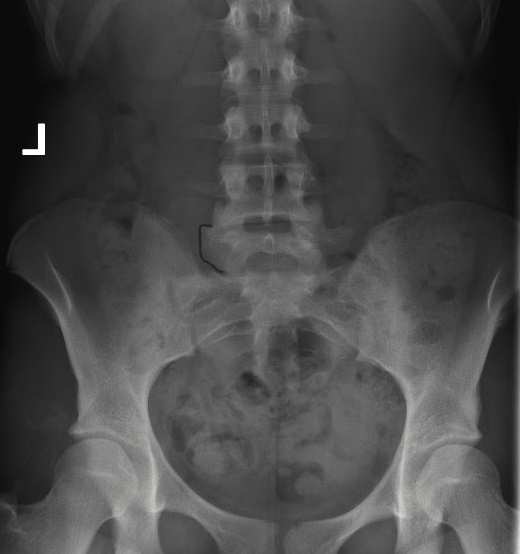

The below radiograph is the patient after surgery. Notice the absence of the large transverse

process/Bertolotti’s.